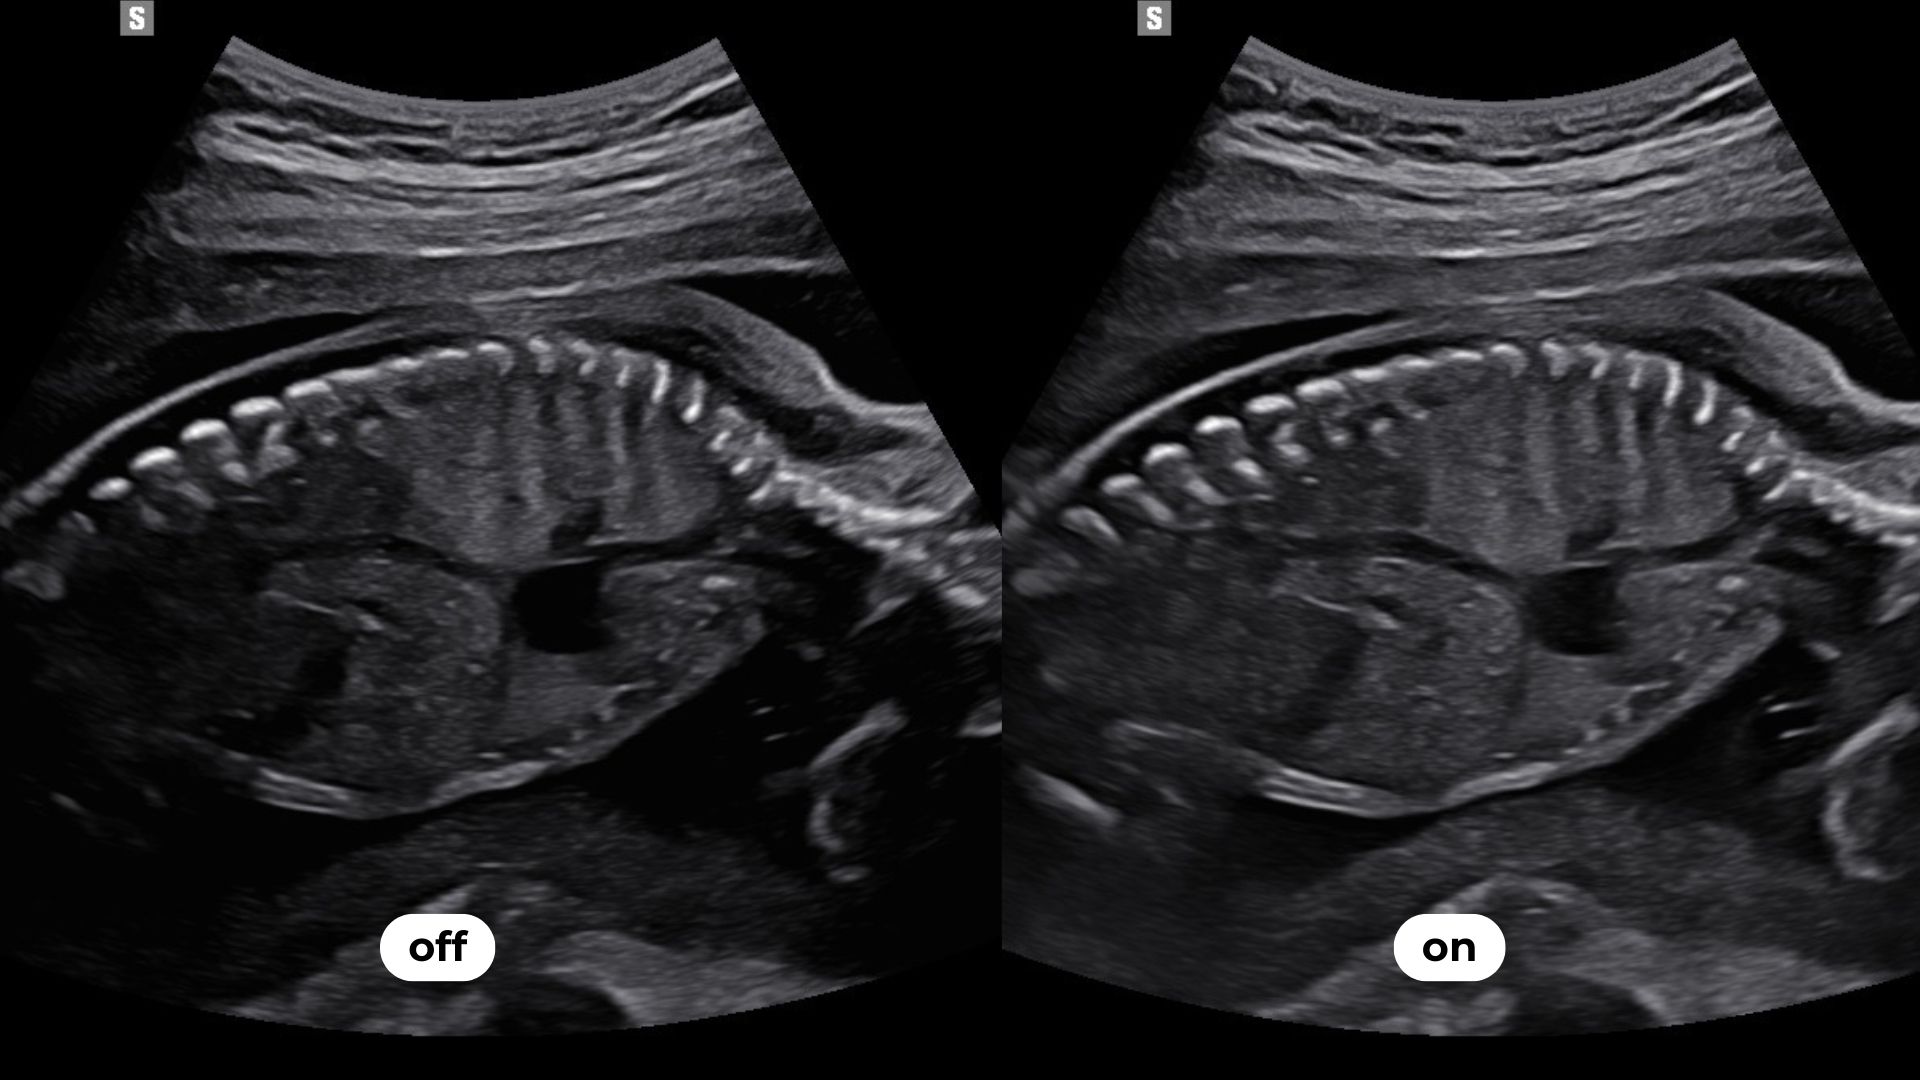

permet une sommation d’images réalisées sur des bandes de fréquences différentes et limite les surexpositions et atténuations du signal. Cet outil met en évidence des zones habituellement masquées comme les contours de la boîte crânienne.